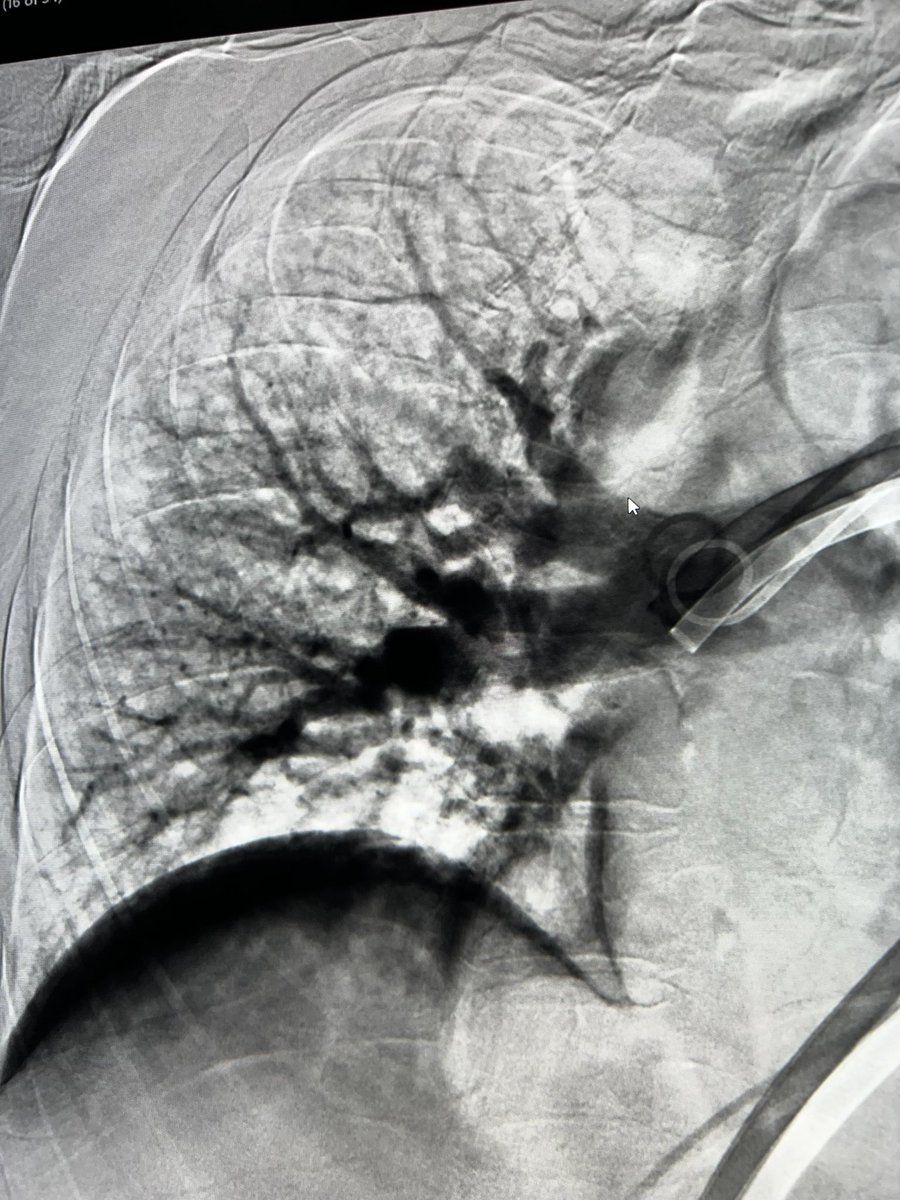

Large volume IVC thrombectomy and mod sed TIPS done same session - patient was able to be discharged and make it to her sons wedding - she fit much better into her dress with no ascites!